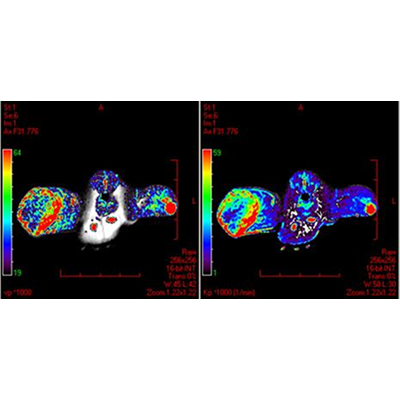

DCE-MRI with a new macromolecular contrast agent in a rat colorectal cancer model. Data courtesy of Drs Wim Ceelen and Peter Smeets, Gent University Hospital, Belgium.